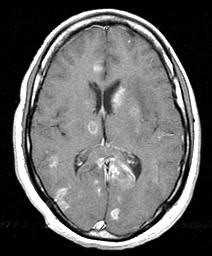

МРТ головного мозга. Тот же пациент. Аксиальная Т1-взвешенная МРТ с контрастированием.

МРТ головного мозга играет ключевую роль в выявлении, оценке распространения и прослеживания динамики герпетического энцефалита. При МРТ головного мозга типичные черты герпетического энцефалита: высокий сигнал от височной доли на Т2-взвешенных МРТ, чаще одностороннее поражение. Поскольку эта зона на МРТ соответствует области Вернике, то у пациента наблюдается афазия и другие речевые расстройства. На МРА нарушений проходимости сосудов не отмечается. МРТ в СПБ при герпетическом энцефалите проводится как в условиях стационара при тяжелом состоянии, так и амбулаторно, в том числе в открытом МРТ. Центры МРТ СПб не имеющие опыта МРТ головного мозга при инфекционных заболеваниях нередко принимают их за опухоли, что ведет к неверной тактике лечения.